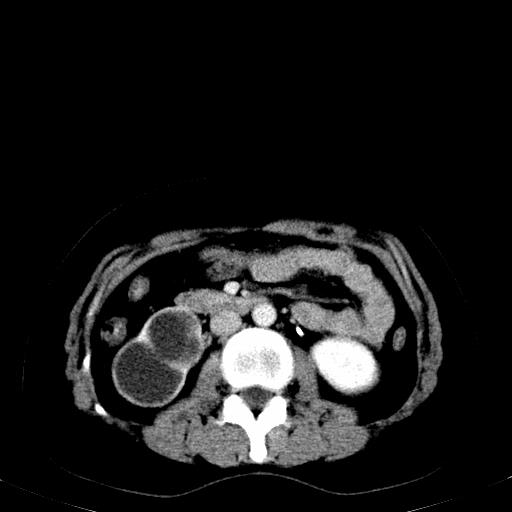

患者体检发现右肾体积增大,怀疑右肾积水

右肾多发囊肿,左肾、左输尿管结石

右肾重度积水,以肾盏积水明显,有分隔,上段输尿管轻度扩张,管壁增厚,考虑肾结核可能,请结合尿检查,胸部拍片排除肺结核。

右肾重度积水,建议ct向下扫描或逆行造影,左肾及左输尿管结石 .

1)不排除右肾结核可能。2)左肾及左输尿管上段结石?

要排除右肾结核可能

左肾不是结石,是造影后改变.右肾积水,功能仅存.

右肾积水、左侧肾脏结石,建议进一步检查原因除外左肾结核可能